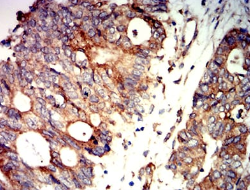

PRKAB2 Mouse Monoclonal antibody[8F5B2]

IHC    1/200 - 1/1000